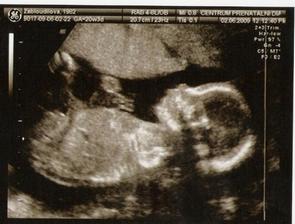

23.6.09 jsme ve 24 týdnu, čekáme chlapečka a bude se jmenovat Jakub.